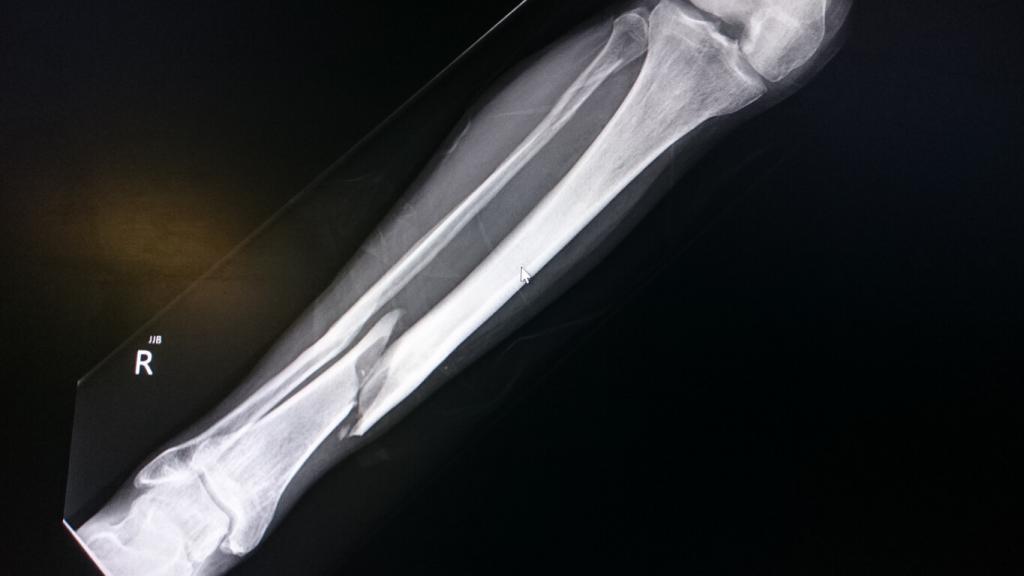

Fractures of the Tibia/Fibula Musculoskeletal Key

From musculoskeletalkey.com

Fractures of the Shaft of the Tibia and Fibula Musculoskeletal Key Fibula Fracture Cast Time Because of this and unlike other types of injuries and conditions, a broken fibula usually requires six weeks to three months. Fibula fracture healing time depends on the complexity of the break and how quickly you get treatment. There are lots of factors that can affect how long it takes your. Repetitive stress fractures are also common. Most tibia or. Fibula Fracture Cast Time.